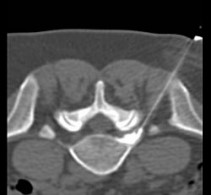

Under computer tomographic or magnetic resonance imaging control, drugs are injected with millimeter precision into the neuralgic points of the spine using fine injection needles. In many patients, this can result in significant pain relief or even freedom from pain. All pain therapy treatments can be carried out on an outpatient basis without any problems due to the low complication rates. A treatment takes a maximum of 10 to 30 minutes.

Periradicular therapy (PRT) is used as a pain therapy procedure for a herniated disc, but also for other back disorders. Here, painkilling and anti-inflammatory drugs are injected with millimeter precision into the painful nerve root under computer or magnetic resonance imaging control. Corticosteroids and long-acting local anesthetics are used. The corticosteroids reduce the swelling of the irritated nerve root, while the local anesthetics reduce the local radiation of pain.

These interventions are CT-assisted, in which a thin special needle is positioned directly on the corresponding nerve plexus (neck, thorax, abdomen, or pelvis) under local anesthesia, and a mixture of local anesthetic and highly concentrated alcohol solution is injected locally. The alcohol solution leads to chemical obliteration of the nerve plexus and thus to pain reduction. The local anesthetic leads to immediate pain reduction when indicated and performed correctly and thus has diagnostic value. For this reason, the procedure is often performed in two stages.